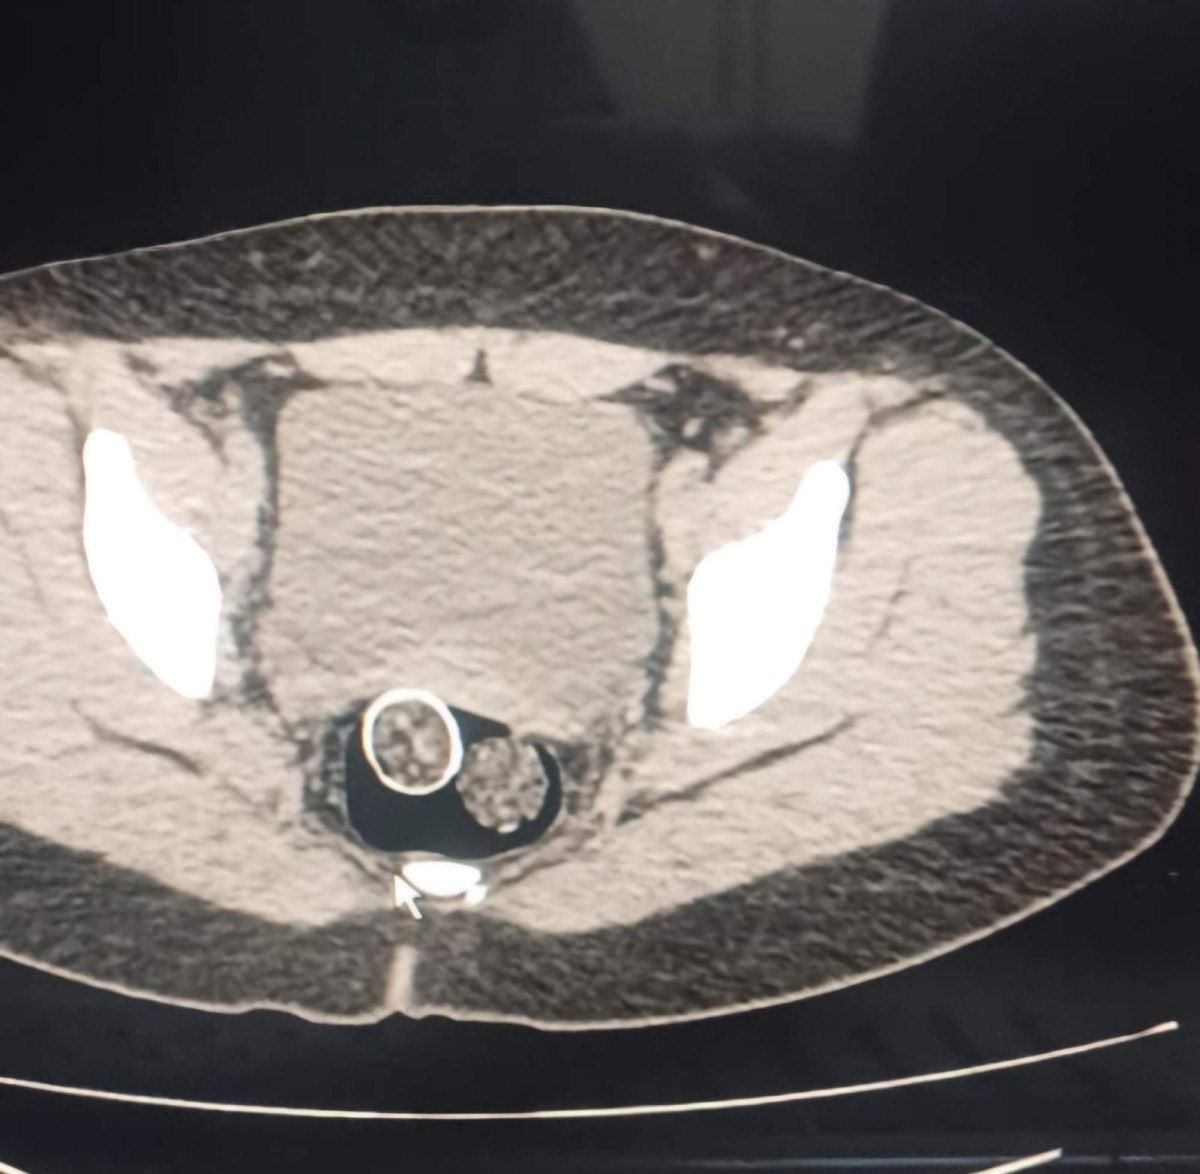

Gözaltına alınan iki şahsın iç beden muayenesinde ve kullandıkları iki araçta yapılan incelemelerde, rahimde ve midede uyuşturucu madde tespit edildi.